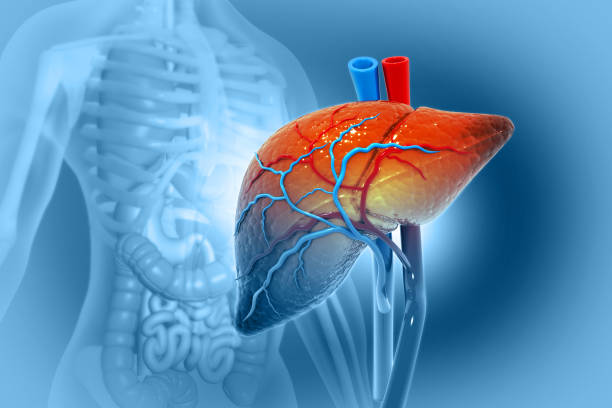

간경화 초기증상 10가지 총정리

간경화 초기증상은 증상이 나타나지 않거나, 미미한 증상만 나타나기 때문에, 무시하고 지나치기 쉬운 경우가 많습니다. 하지만, 이러한 초기 증상을 간과하면 질병이 진행되어 치료가 어려워질 수 있습니다. 따라서, 간경화 초기증상을 발견하면 적절한 검사와 치료를 받아 조기에 질병을 예방하고 치료할 수 있습니다. 따라서 이번 시간에는 간경화 초기증상에 대해 자세히 알아보도록 하겠습니다.